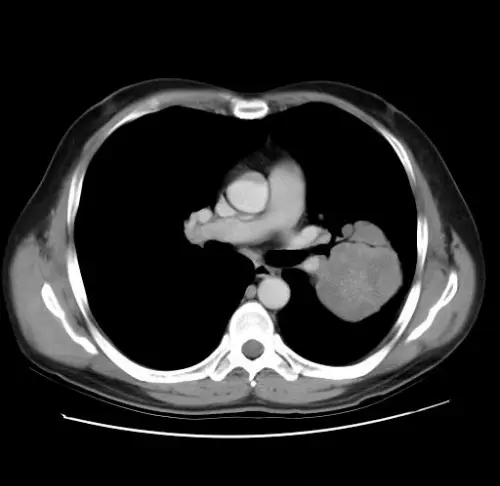

胸部橫斷面CT

- 病灶位於右肺門附近,呈實質性團塊狀,密度高於水(遠高於0 HU),邊緣可見不均勻增強,無液體衰減特徵,確為軟組織實質病灶,而非CT上HU值接近水或低於20 HU的液體 ([peeref.com](https://www.peeref.com/wor